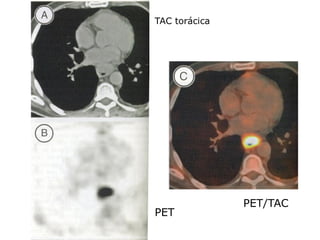

TAC torácica

PET/TAC

PET

Exames. trânsito esofágico; endoscopia ebiópsia / citologia; broncoscopia; TAC toraco-abdominal; ecografia endoesofágica; PET/TAC; toracoscopia.

TAC torácica PET/TAC PET

Estadiamento Sistema TNM; T (eco); N(eco – gânglio suspeito se > 1 cm, hipoecoide e homogéneo, arredondado; TAC – gânglios à distância); M (TAC – metástases hepáticas, pulmonares e ósseas). Acuidade dos exames para o estadiamento tumoral .